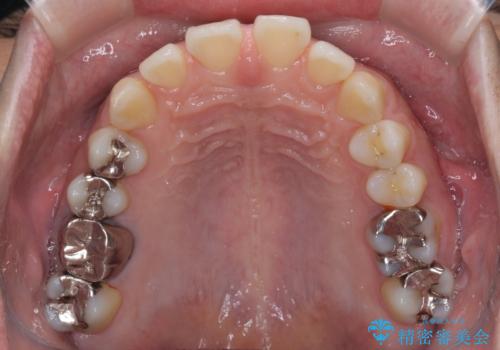

深い咬み合わせと前歯の隙間 ハーフリンガルによる矯正治療

- 咬み合わせにより上顎正中に隙間ができているとのことで来院された患者様です。

インビザラインは自己管理が煩わしく、表側のワイヤー装置は目立つので避けたいとのことで、上顎だけが裏側装置のハーフリンガルにて矯正治療を行うこととしました。